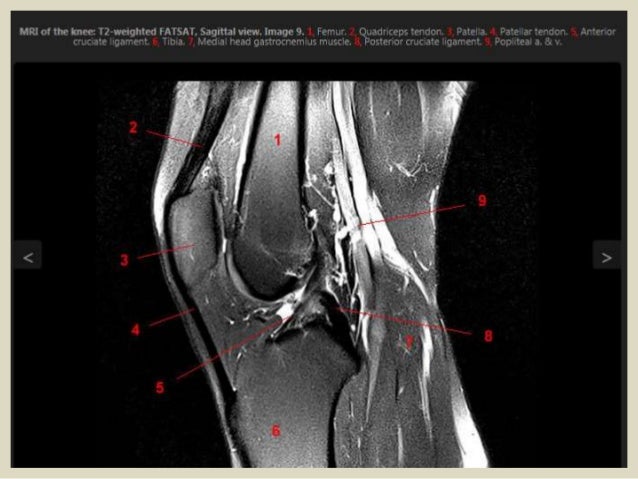

Паховая связка на мрт - фото презентация